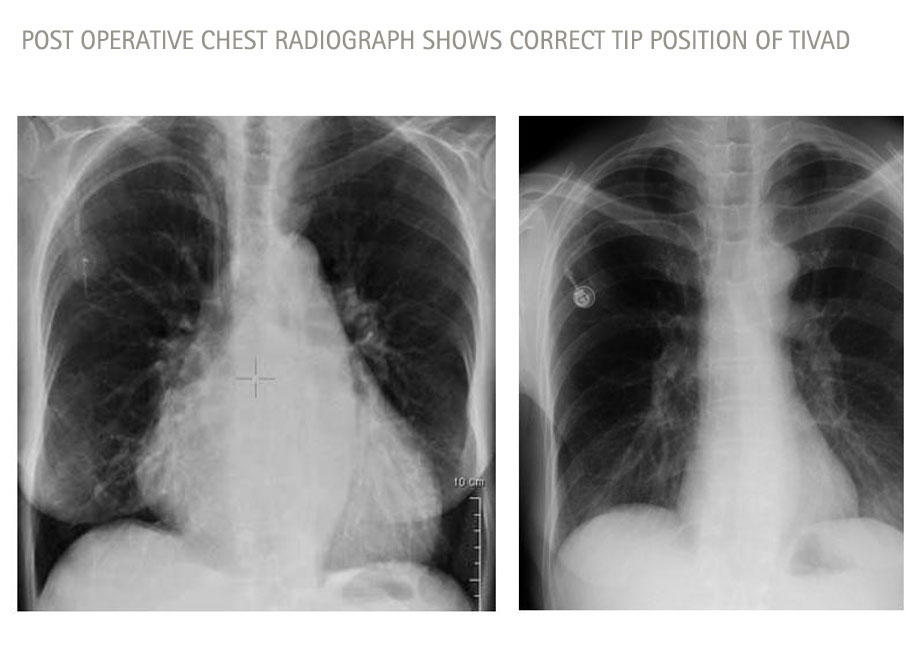

Medica Image to detect misplaced catheter, chest X-ray, alternatively CT or MRI